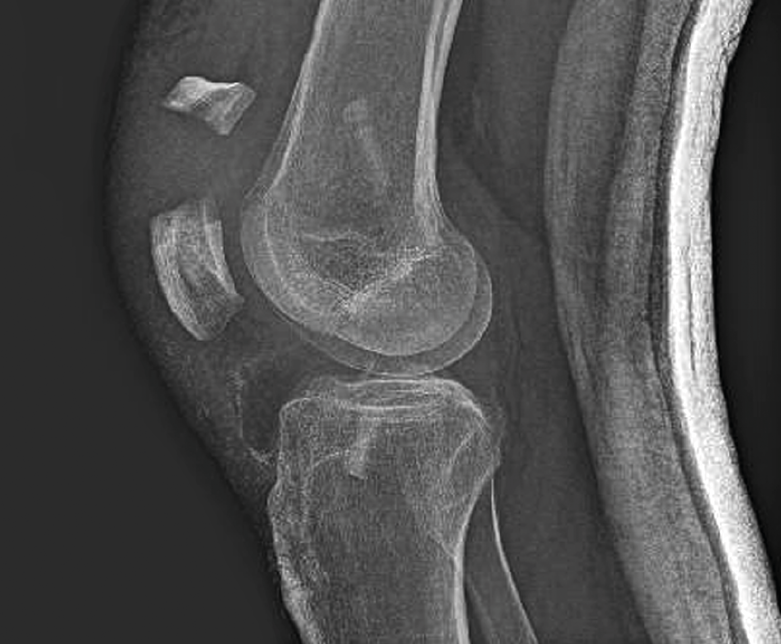

A las 2 semanas reinicia la fisioterapia. En septiembre de 2019, a los 2 meses de la cirugía, sufre una caída casual, presentando una fractura de la rótula derecha (Figura 3), por lo que se lleva a cabo una reducción abierta y osteosíntesis de la fractura en “T” de la rótula derecha. En la cirugía se realiza valoración artroscópica de la plastia del LCA, que se aprecia íntegra.

En el control realizado a los 4 meses de la última cirugía, la rodilla muestra ausencia de derrame, presenta un balance articular en decúbito 130/0/0°, una articulación estable y realiza una extensión activa de la rodilla y una flexión activa de la cadera. Se palpan los alambres de cerclaje, que protruyen. En ese momento, la Rx muestra una consolidación precaria.

Figura 1. A y B: la radiografía muestra una fractura metafisodiafisaria espiroidea proximal tibia, no desplazada; C: en la resonancia magnética se ve la línea de fractura que afecta la cortical posterior de la tibia.